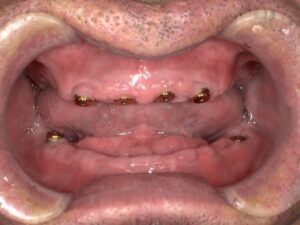

実際の症例です。

レントゲン写真上でも全顎的に重度の歯周病と診断して、IOD治療を選択されました。

残存歯を抜歯後、上顎は4本、下顎は2本インプラントを埋入しました。